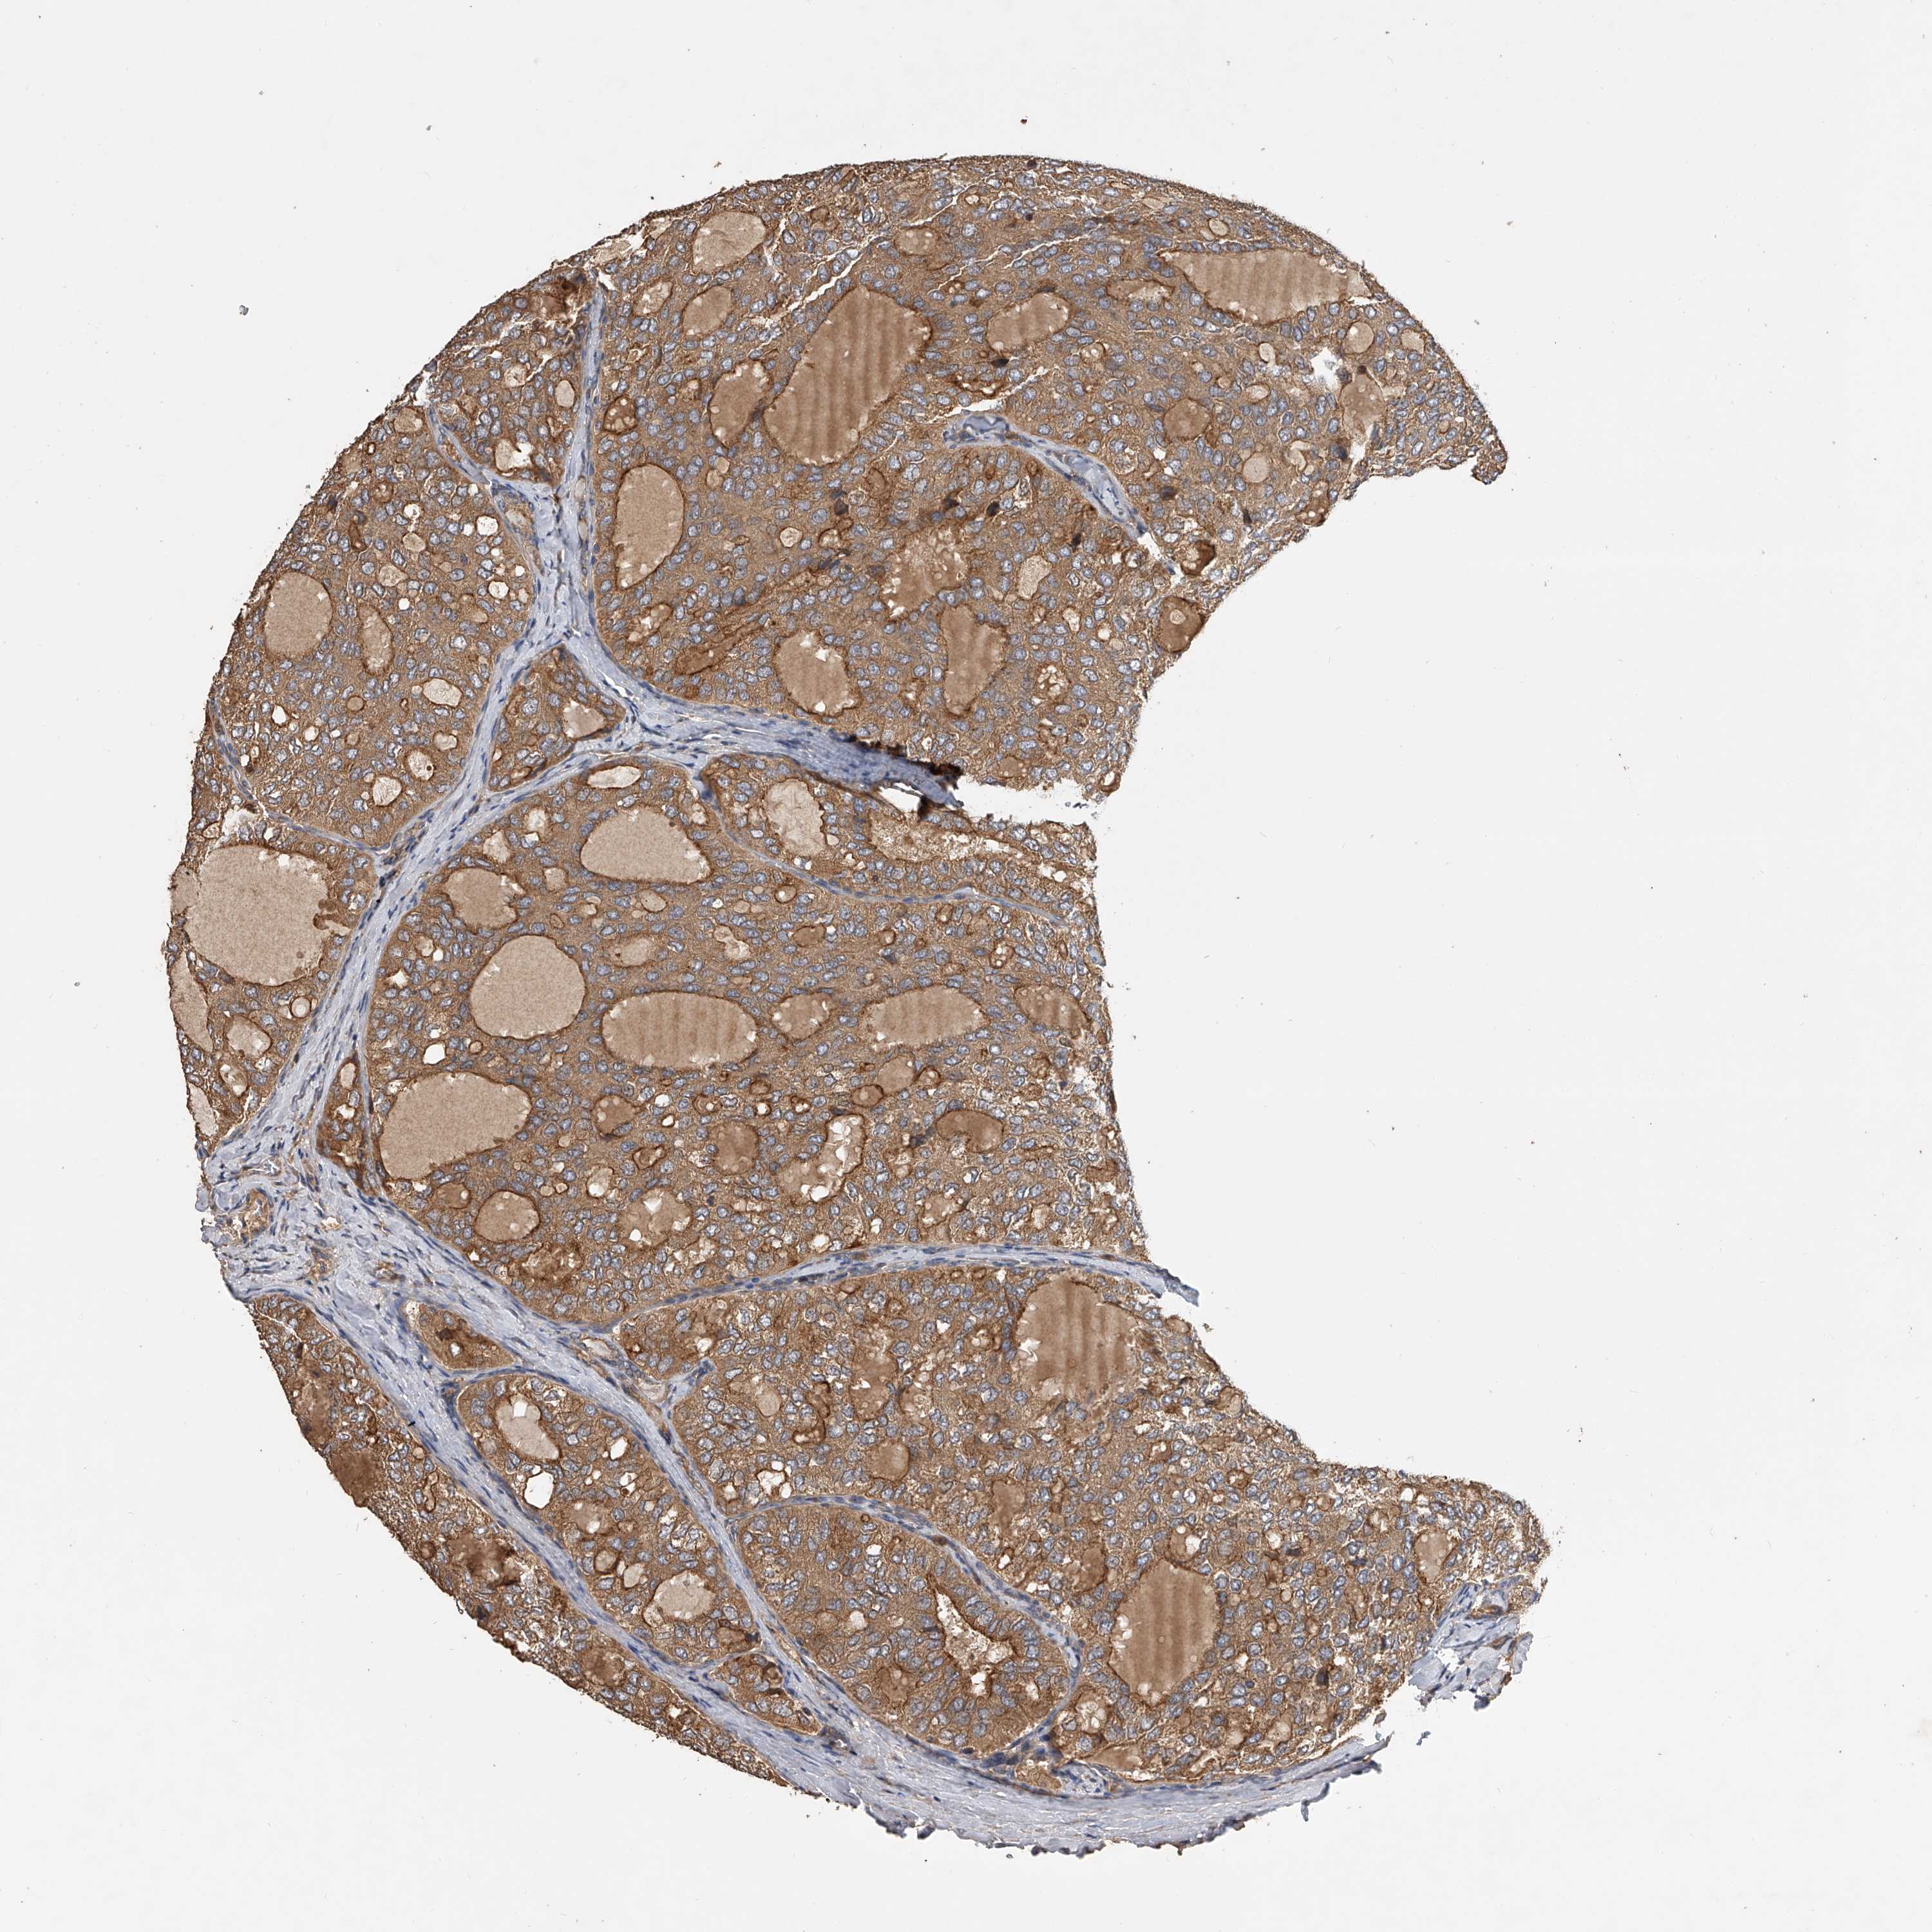

THYROID CANCER - Protein expressioni

A mouse-over function shows sample information and annotation data. Click on an image to view it in a full screen mode. Samples can be filtered based on level of antibody staining by selecting one or several of the following categories: high, medium, low and not detected. The assay and annotation is described here.

Note that samples used for immunohistochemistry by the Human Protein Atlas do not correspond to samples in the TCGA dataset.

Antibody stainingi

Antibody staining in the annotated cell types in the current human tissue is reported as not detected, low, medium, or high, based on conventional immunohistochemistry profiling in selected tissues. This score is based on the combination of the staining intensity and fraction of stained cells.

Each image is clickable and will lead to virtual microscopy that enables deeper exploration of all samples and also displays staining intensity scores, fraction scores and subcellular localization as well as patient and tissue information for each sample.

Antibody HPA029412

Antibody CAB034366

Staining

High

Medium

Low

Not detected

Intensity

Strong

Moderate

Weak

Negative

Quantity

>75%

75%-25%

<25%

None

Location

Nuclear

Cytoplasmic/membranous

Cytoplasmic/membranous,nuclear

Papillary adenocarcinoma, NOS

Follicular adenoma carcinoma, NOS